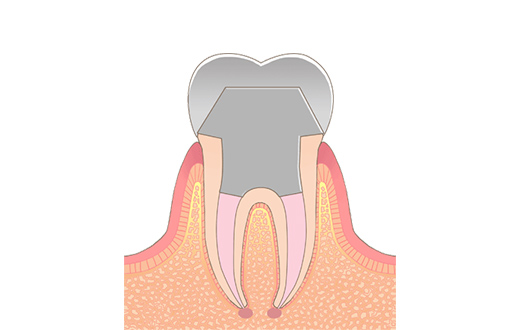

STEP07被せ物の装着

出来上がった被せ物を調整して装着していきます。まず、被せ物と歯に隙間がないかを確認し、次に隣り合った歯との間隔を確認します。その後、噛み合わせを調整して、接着剤で固定します。

歯が無かった部分に歯が入るため、最初はきつく感じたり、違和感を覚えることもありますが、しっかり調整すれば、徐々に慣れてきます。